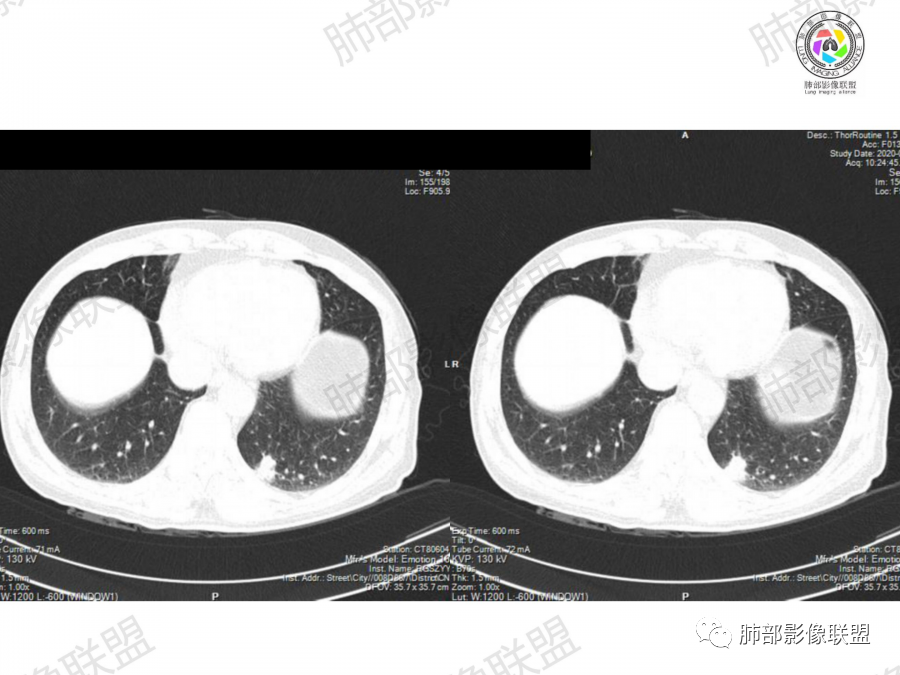

晨读,63岁男性,大量吸烟史,无症状,体检左下肺孤立结节,有分叶,棘突,疑似有血管穿行,考虑肺癌,腺癌?但部分平直,融合,鉴别隐球菌。

实性结节,短毛刺,分叶,腺癌?

鉴别:炎性肉芽肿(外缘平直,糊墙?)

晨读:左肺下叶胸膜下实性结节影边缘毛糙,有毛刺,分叶,近段支气管未见显示,可能堵塞,远端宽基底与胸膜相贴,边缘平直,部分彭隆,病灶局限、单发,无增强,不好判断肿瘤血供,临床男性,63岁,无症状,体检发现,有吸烟史,考虑恶性:腺癌,鳞癌,小细胞肺癌,鉴别:肺隐球菌建议增强及穿刺检查。

晨读:左下肺病变,边缘平直,糊墙征明显,晕征不明显,首先也要考虑炎性病变,病人不明显症状,考虑慢性炎症,密度好像比较均匀,建议增强,隐球菌多糖荚膜试验。如果要排除肿瘤的话,排除腺癌

老年男性,吸烟史。左下肺外周结节,糊墙,部分边缘平直、部分膀隆,见分叶,支气管截断?部分边缘似乎有GGO,内部情况不详。整体考虑恶性,腺癌可能性大,注意鉴别鳞癌、炎性肉芽肿。

老年男性,左肺下叶胸膜下团块,有膨隆有收缩,局部细支气管似截断,边缘少许毛刺,重建整体平直收缩为主,胸膜糊墙,首先考虑炎性肉芽肿,长期吸烟史,又是老年男性,肿瘤是必须警惕的,常规治疗后复查。

老年男性,左肺下叶近胸膜下结节,边缘收缩平直为主,胸膜糊墙,支气管显示不清,病灶密度均匀,首选考虑炎性肉芽肿,鉴别肺癌。

左肺下叶胸膜下结节,有膨隆有收缩,分叶毛刺,老年男性,首先考虑腺癌,鉴别炎性肉芽肿,常规治疗后复查。

晨读病例,老年人 ,吸烟史,左肺下叶结节影,密度均匀,边缘毛糙,周围可见长毛刺,病灶边缘分叶,局部膨隆,部分边界平直,收缩,病灶相邻胸膜处可见糊墙征象,病灶近肺门处见支气管堵塞,考虑恶性病变,周围型肺癌:鳞癌伴肺不张>腺癌,鉴别隐球,炎性假瘤。

胸膜下结节,分叶,细毛刺,似有晕,纵向结节融合表现,支气管顶峰进入,猜肉芽肿,隐球菌?

1、老年男性,大量吸烟史,无症状,体检左下肺孤立结节。

2、影像表现:无肺气肿背景、定位左肺下叶后基底段,不规则结节、与支气管关系不明确,部分边缘平直、部分膨隆,病变与胸膜宽基底相连,病变与胸膜糊墙征,病变周围见细、长、软毛刺,病变密度比较均匀。影像总体倾向炎症、符合肺组织慢性炎症伴机化。